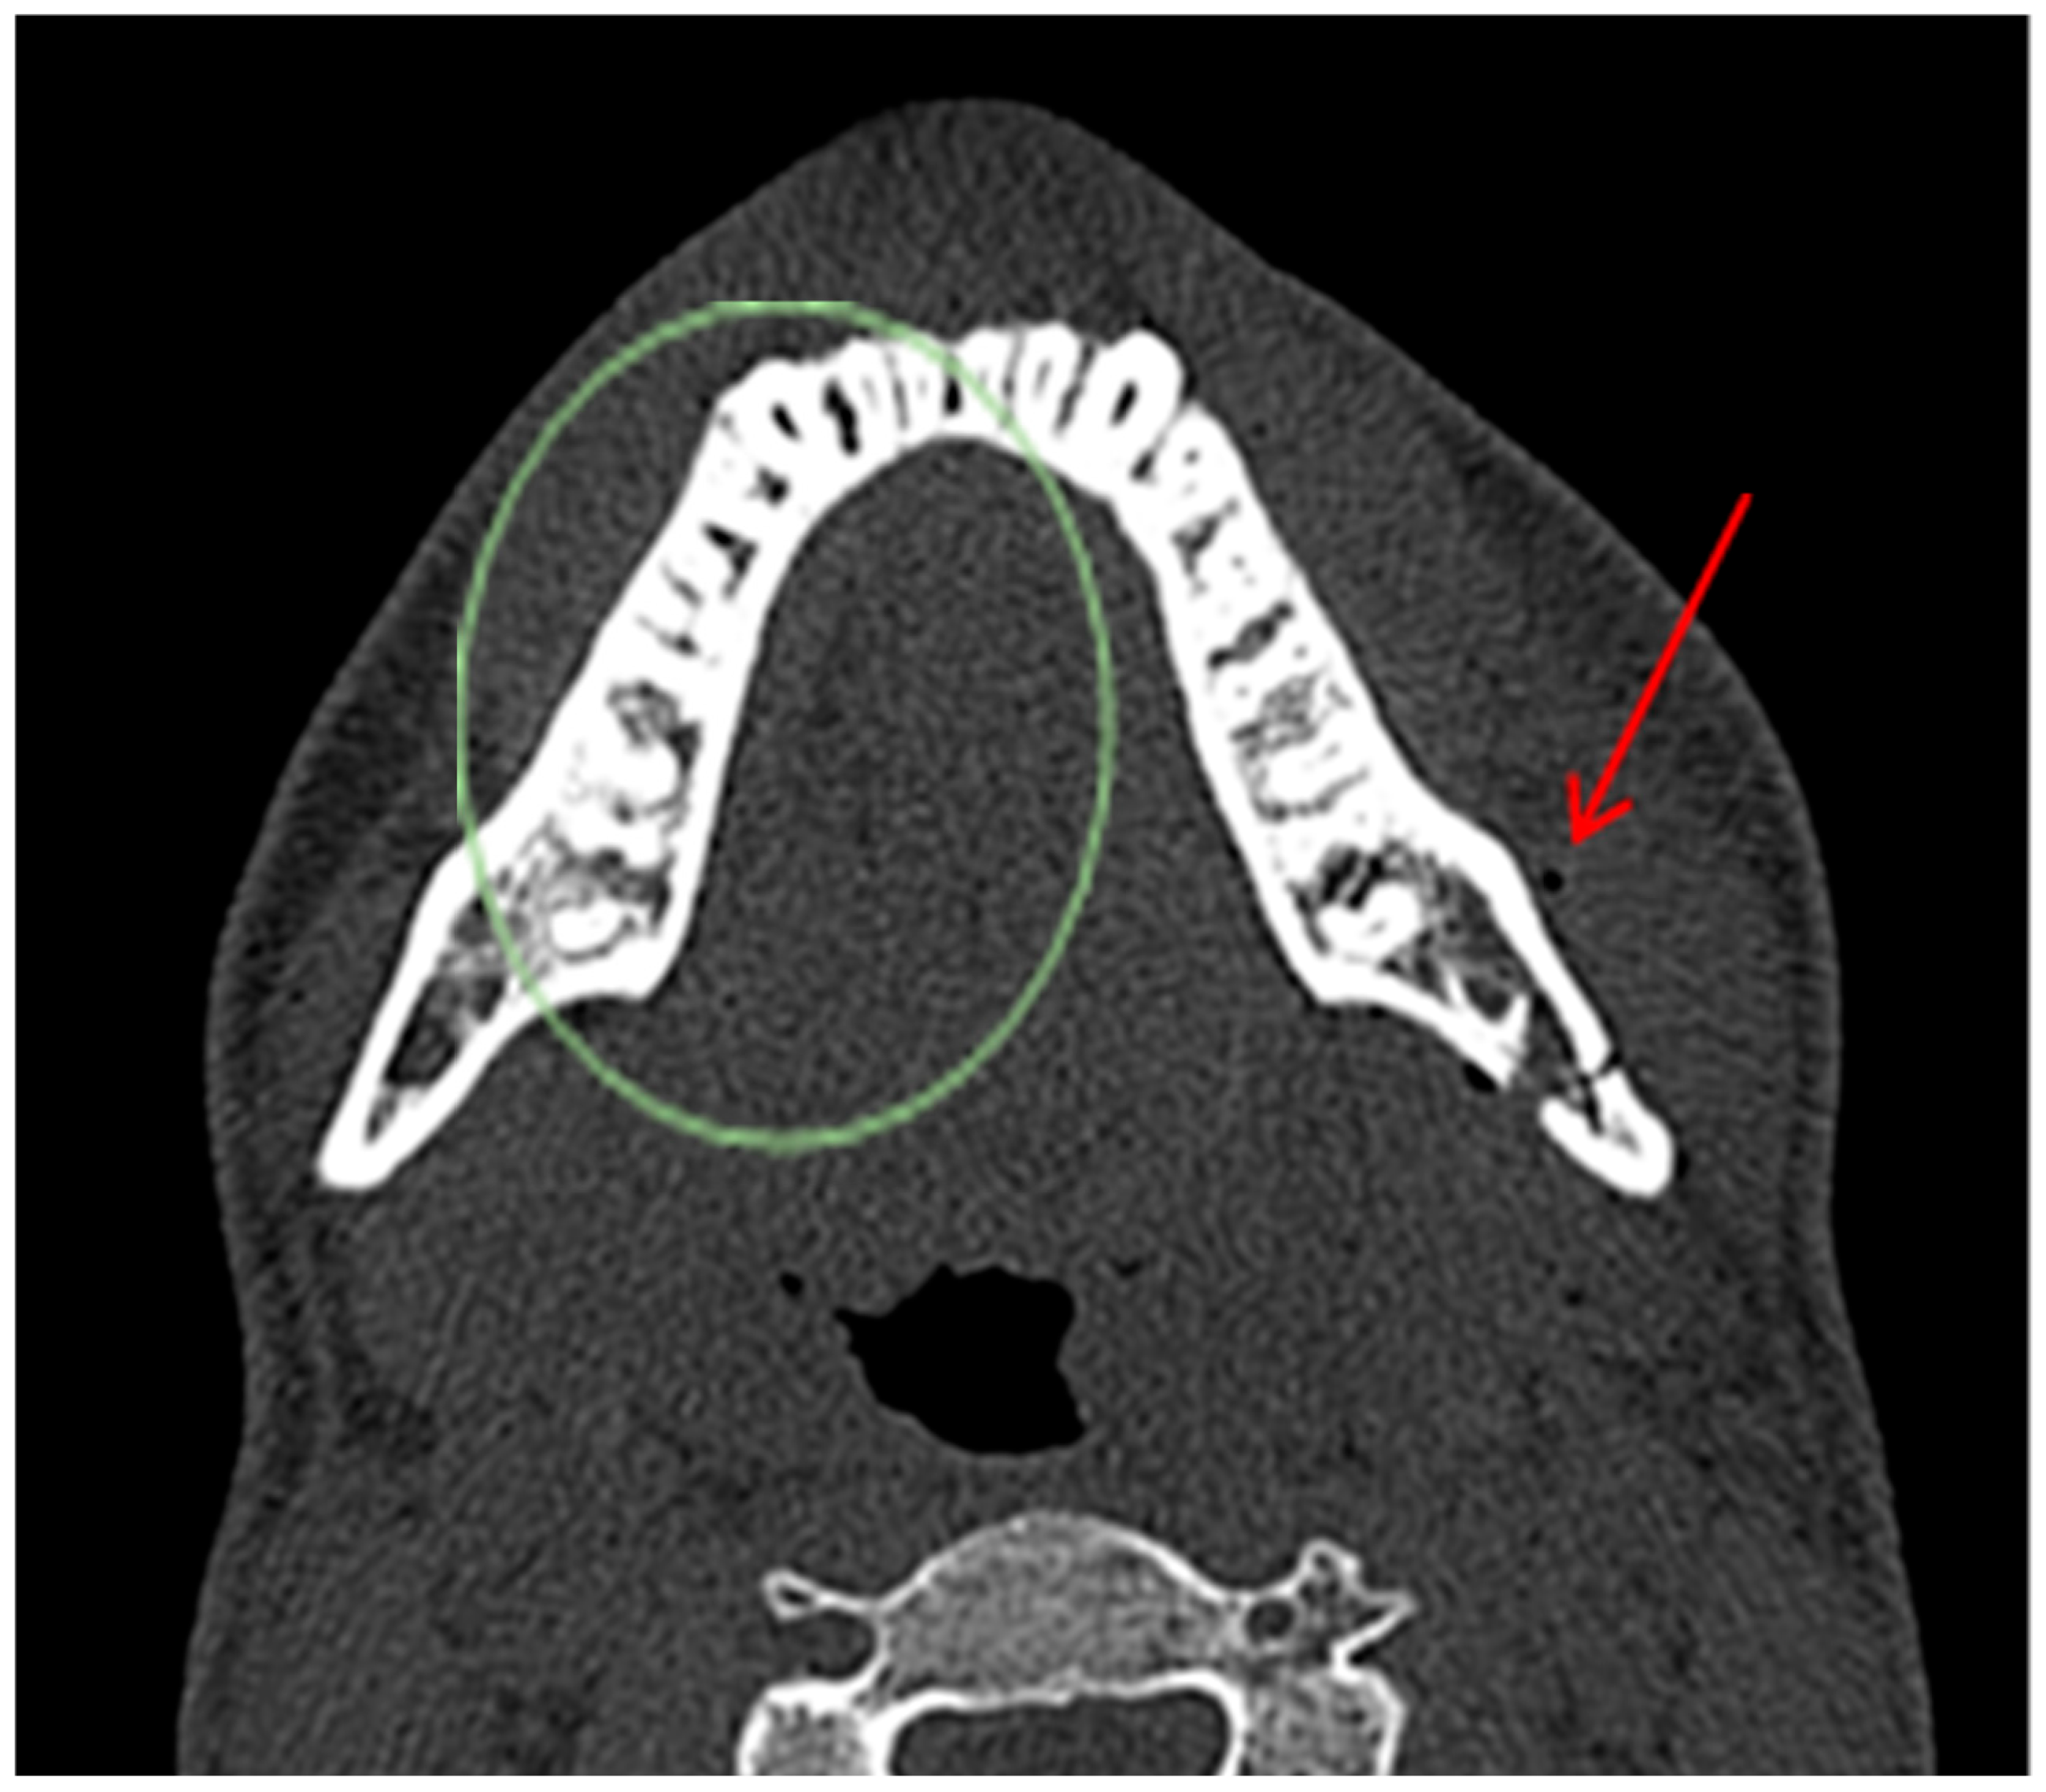

Diagnostic Utility of the “Air Sign” as a Radiological Indicator for Mandibular Body and Angle Fractures

- Gontarz, M.; Bargiel, J.; Gąsiorowski, K.; Marecik, T.; Szczurowski, P.; Zapała, J.; Wyszyńska-Pawelec, G. “Air Sign” in Misdiagnosed Mandibular Fractures Based on CT and CBCT Evaluation. Diagnostics 2024, 14, 362. [Google Scholar] [CrossRef]